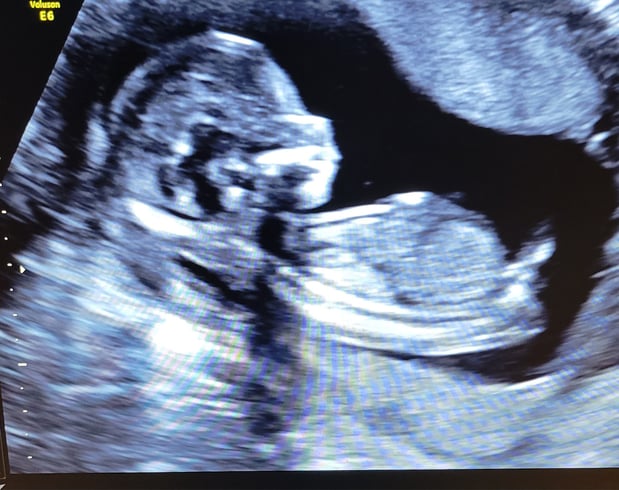

Tasha Crump, is registered by the American Registry of Diagnostic Medical Sonographers (ARDMS) and have over 18 years experience in medical diagnostic sonography specializing in Maternal Fetal Medicine. She is a highly proficient in the art of 3D 4D ultrasound. Tasha has practiced and trained in NYC's top ranked hospitals including Columbia Presbyterian. At Love at First Sight Imaging Studio you'll be in a very comfortable and calming atmosphere for you and your family to bond with your baby. We have state of the art equipment with HD Live to image unbelievably realistic views of your baby. You will fall in Love at First Sight.